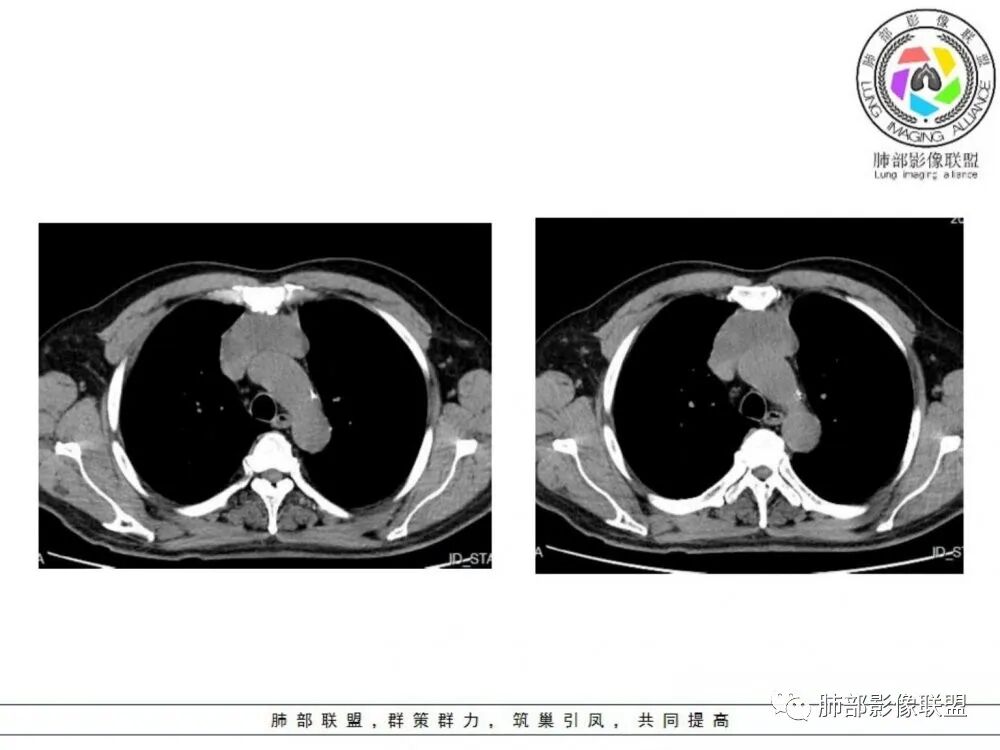

男性患者,65岁,前胸后背疼痛一个月。影像学前上纵隔分叶状的软组织肿块,肿块形态怪异,偏软,位于大血管间隙前,并有向血管后间隙发展的趋势,平扫CT值为40左右,增强扫描中心部未见强化,周围轻度的强化,约为50左右。前上纵隔的疾病谱包抬胸廓内甲状腺肿、胸腺瘤/癌、畸胎瘤、淋巴瘤。少见的心包囊肿或支气管囊肿。根据肿块的形态及强化特点,首先还是排除了胸内甲状腺肿及胸腺来源的肿物,这类的肿物强化比较明显。畸胎瘤成分比较复杂,具有软组织钙化或者脂肪类的组织,这个肿物虽然在平扫的时候好像有斑点状的钙化灶,但是总体成分还是比较单一,所以还是排除畸胎瘤的诊断。所以这样的情况是考虑:淋巴类的肿瘤,注意排除心包的囊肿或支气管来源的囊肿。

老年男性患者,前膈软组织肿块,边缘轮廓不光整,边界似乎尚清晰,内见小点状钙化灶,平扫密度欠均匀,增强后轻度强化表现,边缘有些斑片状的高强化区。综合考虑胸腺瘤或胸腺鳞癌,神经内分泌癌强化弱了一些。患者年龄较大,生殖细胞肿瘤不考虑,淋巴瘤血管包绕不够,可能性不大

老年男性,前胸后背痛一个月,前纵隔不规则肿块,分叶,向纵隔血管间隙进入,且与纵隔血管分界不清,增强边缘轻度强化,中间可见无强化区,似见点状钙化,PET为高代谢,考虑为来源于胸腺,胸腺瘤或胸腺鳞癌可能

临床,老年男性,病史一月。1 定位,骑跨大血管,大部分位于胸腺区域内,周边部分胸腺脂肪有混浑浊,起源于胸腺区的组织应该没有问题。2 定性 。恶性征像,分叶,大血管侵润,pet高代谢,左侧庄层胸膜增厚(类似脑膜瘤的脑膜尾征,良性表现?)。良性征像,病灶均匀,无明确坏死?综合恶性征像多些,考虑恶性可能大。病灶分两部分,部分层面似有明确分割,两个性质的病灶长一块,还是,一个病灶两种不同成分?一个病灶伴均匀坏死?CT值41hu,坏死好像高了点,一个病灶,相同成分,只是血管分布不同,增强是持续流入型强化。纤维类?编不下去了,岔路太多,祭出法宝按概率蒙吧:侵袭性胸腺瘤>神经纤维瘤>乏血供CD

老年男性,定位前纵隔,似乎有点塑形生长,肿块与大血管分界欠清,上腔静脉局部包绕受压,侵犯?增强扫描低强化。考虑恶性,胸腺癌可能。鉴别淋巴瘤。

老年男性患者,前膈软组织肿块,边界似乎尚清晰,内见小点状钙化灶,平扫密度欠均匀,增强后轻度强化表现,边缘有些斑片状的高强化区,考虑胸腺瘤或胸腺癌。

前纵隔不规则肿块,分叶,与纵隔大血管脂肪界面消失,轻度不均匀强化,未见纤维分隔,考虑胸腺癌或胸腺瘤,鉴别淋巴瘤

老年男性,前纵隔不规则软组织肿块影,密度欠均匀,与大血管分界欠清,上腔静脉局部包绕受侵,增强扫描不均匀轻度强化,PET-CT高代谢。考虑恶性肿瘤性病变,胸腺癌可能。鉴别淋巴瘤。

前纵隔胸腺区分叶状软组织肿块影,轻度不均匀强化,中心可见坏死,边缘不清,病灶与邻近心包见条索影,上腔静脉受侵,上纵隔多发小淋巴结,考虑胸腺鳞癌可能。

中老年男性,前纵隔占位,基本居中,向两侧生长;边缘膨隆分叶,部分边界不清,增强不均匀轻中度强化,坏死区边界不清;周围多发增大淋巴结,考虑恶性。主要在胸腺癌、胸腺瘤、淋巴瘤之间鉴别。病灶偏软,有钻缝样生长,这些征象偏向于淋巴瘤。但此例老年患者,病灶内有点状钙化,缺乏结节堆砌感,倾向胸腺癌诊断。